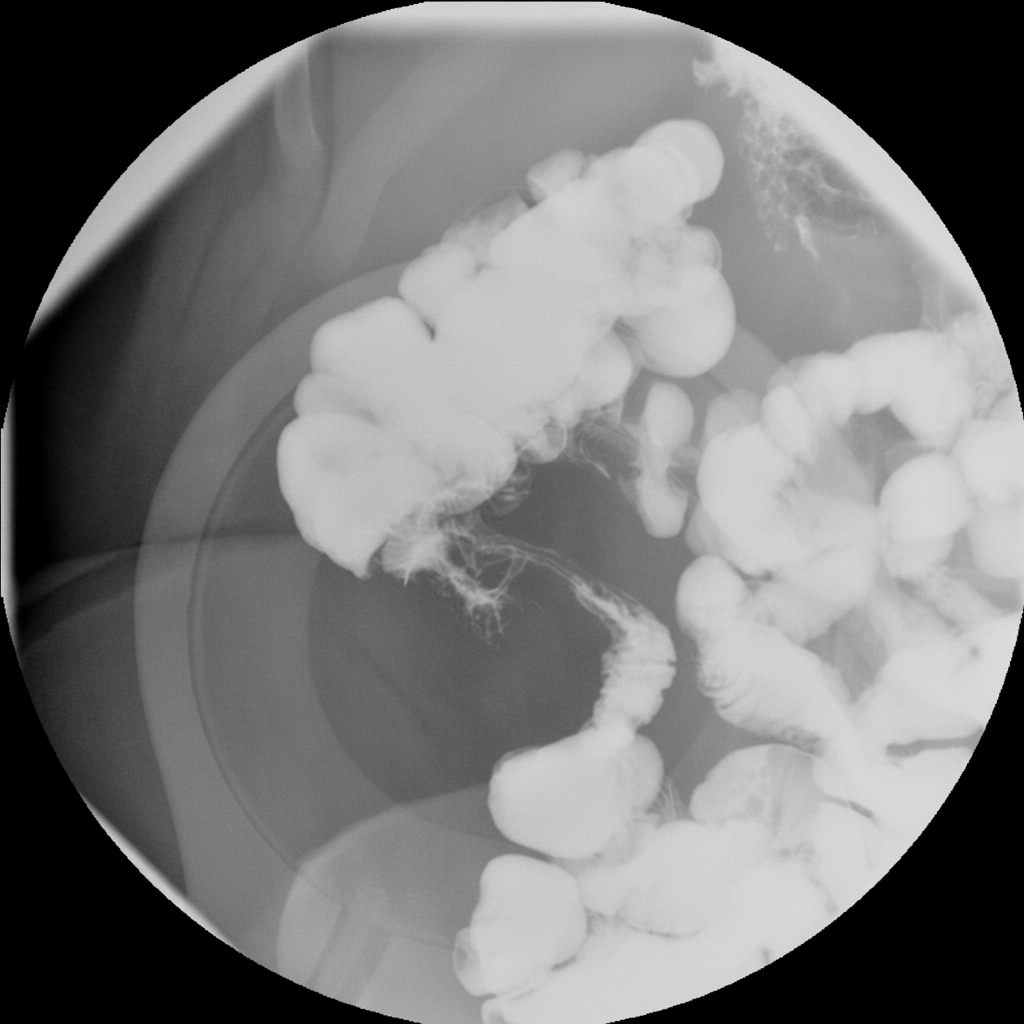

Explanation: The clinical presentation is classic for **Chronic Pancreatitis (CP)**. The diagnosis is based on the triad of chronic abdominal pain, features of exocrine insufficiency (malabsorption/weight loss), and a history of predisposing factors (alcoholism and smoking). [1] **1. Why Chronic Pancreatitis is Correct:** * **Clinical History:** Chronic alcohol consumption is the most common cause of CP. [1] The patient’s history of a prior acute episode 3 years ago suggests a progression from acute to chronic inflammation. * **Exocrine Insufficiency:** Significant weight loss (12 kg) and malabsorption (steatorrhea) indicate that >90% of the pancreatic parenchyma is damaged, a hallmark of late-stage CP. [3] * **Enzymes:** In CP, serum amylase and lipase are often **normal or only mildly elevated** because the pancreatic acinar cells are fibrotic and exhausted, unlike the massive release seen in acute episodes. **2. Why Other Options are Incorrect:** * **Acute Pancreatitis:** Typically presents with acute, severe, constant pain radiating to the back and significantly elevated amylase/lipase (>3x normal). It does not explain chronic malabsorption or long-term weight loss. * **Pancreatic Cancer:** While it presents with weight loss and pain, the 3-year history of abdominal pain and the specific link to chronic alcoholism favor CP. However, CP is a major risk factor for adenocarcinoma. * **Pancreatic Pseudocyst:** This is a complication of pancreatitis. While it causes pain and a palpable mass, it wouldn't typically cause generalized malabsorption unless it causes significant ductal obstruction. **3. NEET-PG High-Yield Pearls:** * **Most common cause:** Alcohol (Adults), Cystic Fibrosis (Children). [1] * **Imaging Gold Standard:** **MRCP** is the non-invasive test of choice to visualize ductal changes ("Chain of Lakes" appearance). [2] * **Most sensitive test for early CP:** Endoscopic Ultrasound (EUS). * **Classic Triad (rarely all present):** Pancreatic calcifications, steatorrhea, and diabetes mellitus. * **Treatment of Malabsorption:** Pancreatic enzyme replacement therapy (PERT) taken *with* meals.